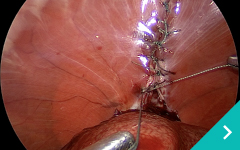

ミニマム創内視鏡下手術は腹腔鏡だけでは対処ができないような手術の際に、お腹にラッププロテクターという器具を設置して行う腹腔鏡と開腹手術を組み合わせた手術です。